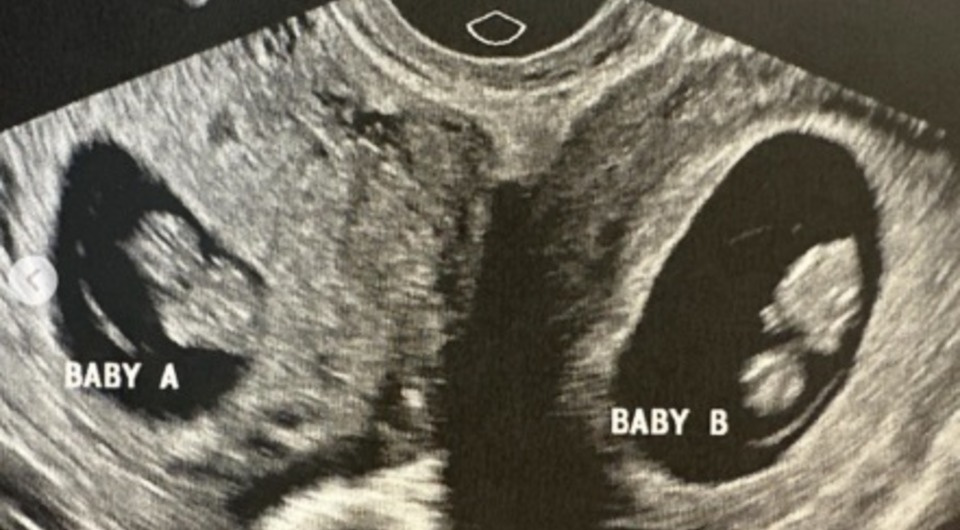

У американки с двумя матками выявили беременность в обеих

Врачи обнаружили, что 32-летняя жительница Алабамы с двумя матками вынашивает ребенка в каждой из них. Как отмечает Science Alert со ссылкой на AFP, такие беременности очень редки — один случай на 50 миллионов. Судя по всему, две яйцеклетки были оплодотворены независимо друг от друга. Сейчас роды протекают нормально, поэтому женщина надеется, что к концу года ей удастся родить естественным путем. Однако высока вероятность, что ей все-таки понадобится кесарево сечение.